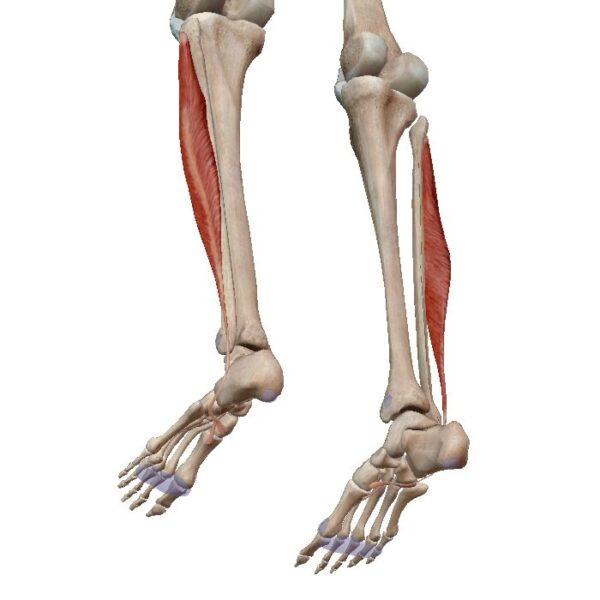

- Inserciones sobre el esqueleto: La mayoría de los músculos se insertan en superficies óseas del esqueleto. Estas inserciones permiten que los músculos generen movimiento y estabilización de las articulaciones. Los puntos de inserción pueden ser crestas óseas, tubérculos, cóndilos, procesos, entre otros. La conexión entre los músculos y los huesos se realiza a través de los tendones, que son estructuras resistentes y fibrosas que transmiten la fuerza generada por el músculo al hueso.

El modo de inserción de los músculos en el cuerpo humano se realiza generalmente a través de los tendones. Los tendones son estructuras fibrosas y resistentes que prolongan el músculo y lo conectan con su punto de inserción. A continuación, se explican ampliamente las características y funciones de los tendones:

- Estructura de los tendones: Los tendones están compuestos principalmente por fibras de colágeno, que les proporcionan su resistencia y firmeza características. Estas fibras están dispuestas en una estructura organizada que les permite transmitir la fuerza generada por el músculo al hueso o a la estructura de inserción. Los tendones suelen tener una apariencia blanquecina, brillante y nacarada.

- Forma y variedad de los tendones: Los tendones pueden presentar diversas formas y características. Algunos tendones son cilíndricos, mientras que otros son aplanados. Además, pueden variar en longitud, siendo algunos muy largos y otros muy cortos. También existen tendones que se extienden en amplias láminas fibrosas. Estas variaciones en la forma y estructura de los tendones están adaptadas a las necesidades específicas de cada músculo y su función en el cuerpo.

- Función de los tendones: Los tendones desempeñan un papel crucial en la transmisión de la fuerza generada por los músculos a las estructuras de inserción, como los huesos o los tejidos conectivos. Gracias a su resistencia y rigidez, los tendones permiten una transmisión eficiente de la fuerza muscular sin pérdida de energía ni retardo en la respuesta. Esto es esencial para el movimiento y la estabilidad del cuerpo humano, ya que garantiza que la contracción muscular se traduzca en un movimiento efectivo.

- Propiedades biomecánicas de los tendones: Los tendones son prácticamente inextensibles, lo que significa que tienen poca capacidad de estiramiento. Esto permite una transmisión directa y rápida de la fuerza generada por el músculo, sin pérdida de potencia ni demora en la respuesta muscular. Además, la rigidez de los tendones ayuda a mantener la integridad estructural de las articulaciones y a resistir las fuerzas de tracción y compresión durante el movimiento.